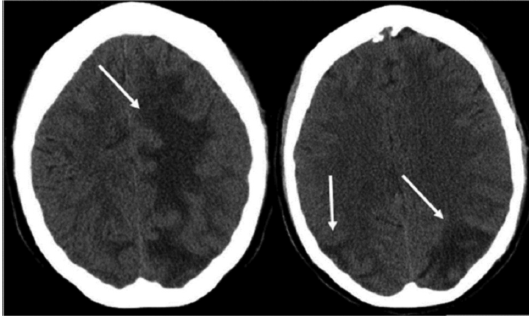

On imaging, PRES manifests as vasogenic edema of subcortical white matter mainly involving posterior and parietal areas of the cerebral circulation and usually showing bilateral and symmetrical distribution.11 There is occasional involvement of frontal lobes, especially around the superior frontal gyrus. Computed tomography (CT) scans often display an initial modality that depicts hypoat-tenuation in the affected areas,12 as shown in Figure 3.

Figure 3. Noncontrast Computed Tomography Images Showing Vasogenic Edema Involving Both Parietal and Occipital and With Extension Into Left Frontal Lobe11